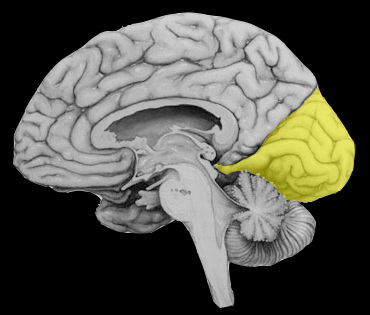

Territoire de l’artère cérébrale postérieure